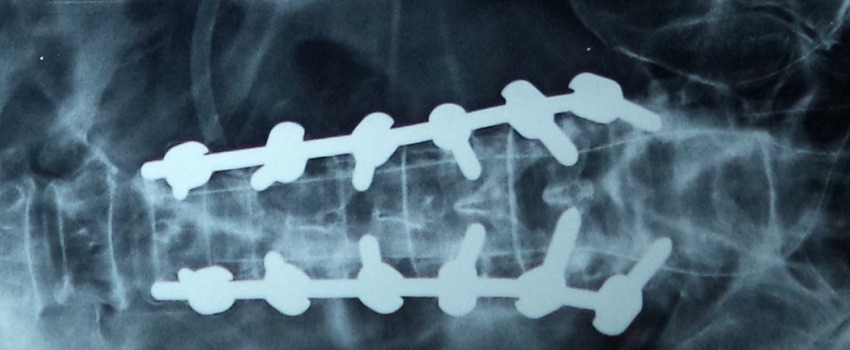

These fractures can be treated very well with the help of Pedicular screw system. This system and the C arm image intensifier equipment are very useful to correct and fix these vertebral fractures in the best possible position. After the spinal fixation, it is possible for the patients to sit and walk very early and the fixation gives very good pain relief.